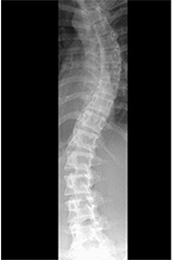

척추 측만증에 대한

방사선 촬영 기능

한눈에 척추의 휘어짐을 볼수 있는 롱패널

SOCLIO의 Lead Line이 척추의 휨 정도를 쉽게 판단할 수 있도록 하며 Radiography에 도출될 수 있도록 Lead Line이 폭넓게 분포되어 있습니다. 또한 2, 3장으로 분할 획득한 영상을 쉽게 조합 가능하며 정밀한 하나의 Spine 이미지를 얻을수 있습니다.